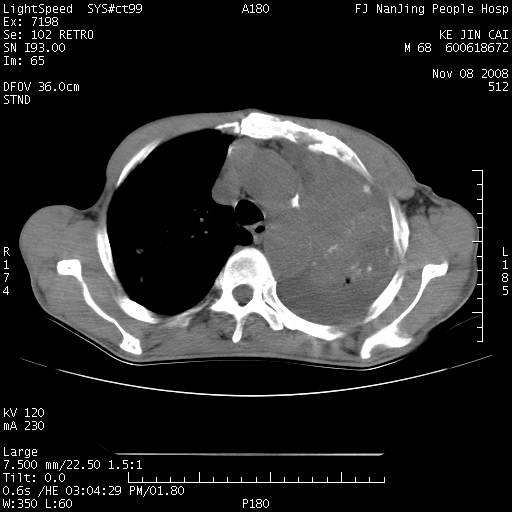

是个很有看头的病例,咋人气那么不旺?没多少人兴趣呢?这个病例几大怪:1   恶性肿瘤侵犯心肌左房怪,心肌一般不会被恶性肿瘤侵犯吧?2   左下肺均匀实变怪,内无含气,有别一般不张实变,含气肺泡完全为液体取代,而非一般不张实变的肺萎陷,冷不丁还以为是肿大的脾脏3   肿瘤本身怪,像tb肺不张4   这么有看头的病例没人气怪。呵呵。

左肺恶性肿瘤侵犯肺动脉,左心房内瘤栓,胸膜转移。